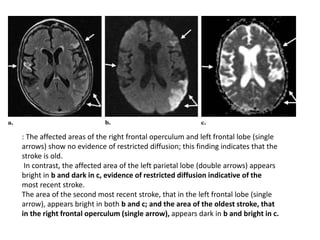

Combination of FLAIR and diffusion-weighted imaging with ADC mapping for depiction of

effects

of multiple strokes.

(a) Axial T2-weighted FLAIR image shows three areas affected by strokes (arrows).

(b, c) Axial diffusion-weighted echo-planar image (b) and ADC map (c) allow

determination of the age of the

strokes

: The affected areas of the right frontal operculum and left frontal lobe (single

arrows) show no evidence of restricted diffusion; this finding indicates that the

stroke is old.

In contrast, the affected area of the left parietal lobe (double arrows) appears

bright in b and dark in c, evidence of restricted diffusion indicative of the

most recent stroke.

The area of the second most recent stroke, that in the left frontal lobe (single

arrow), appears bright in both b and c; and the area of the oldest stroke, that

in the right frontal operculum (single arrow), appears dark in b and bright in c.